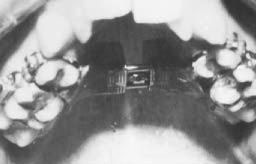

Fig. 2 The palatal stent in position.

Fig. 3 The rapid palatal expansion appliance in position.